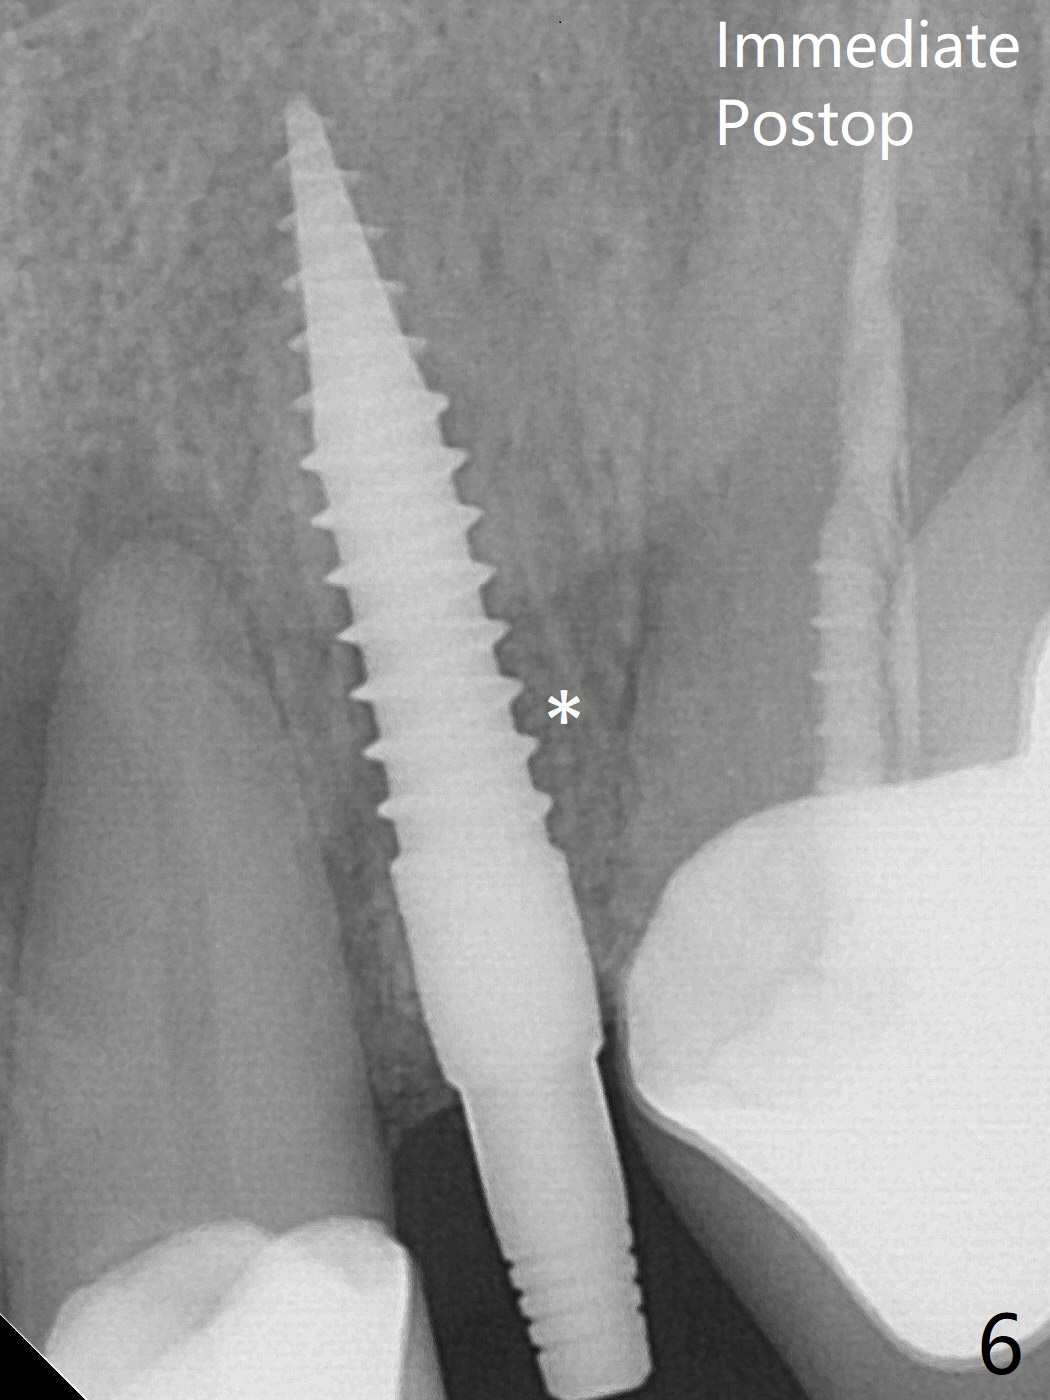

Following further distalization, a 3x14 mm implant is placed (Fig.6; <30 Ncm). Vera Graft will be placed in the remaining socket prior to provisional fabrication (*). The socket outline disappears 7 months postop (Fig.7).